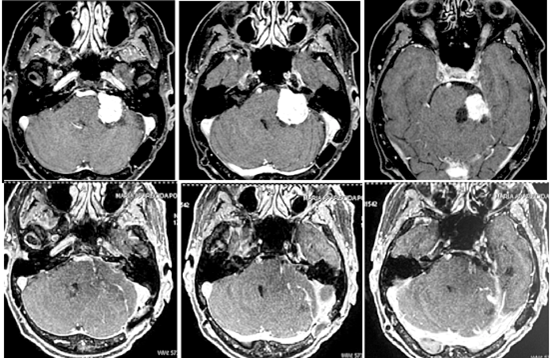

Caso 2

Paciente com 47 anos de idade submetida a duas cirurgias em outro serviço.

Acima ressonância magnética antes da cirurgia mostrando um tumor gigante comprimindo o tronco do cérebro e o cerebelo. Abaixo após a remoção total do tumor.